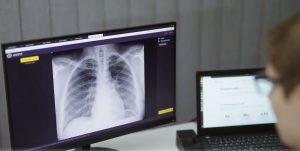

Founded in 2017, Oxipit develops CE-marked AI solutions for radiology, including ChestLink—the world’s first CE Class IIb certified autonomous AI solution for chest X-ray analysis. ChestLink automatically identifies high-confidence normal examinations and removes them from the radiologist’s worklist, enabling specialists to focus on cases that require their clinical judgment. The company has recently expanded its portfolio into CT and musculoskeletal imaging.

Founded in 2017 by experts in medicine and data science, Oxipit is a leader in AI-based medical imaging. The company introduced ChestEye in 2019 for detection of 75 chest X-ray findings and launched ChestLink in 2022 as the world’s first CE Class IIb certified solution capable of identifying normal chest X-rays with 99.9% sensitivity. In 2026, Oxipit expanded its portfolio into chest CT and musculoskeletal X-ray imaging, continuing to support radiologists through workflow-integrated detection, prioritisation, and reporting support in daily clinical practice worldwide. Read more at www.oxipit.ai